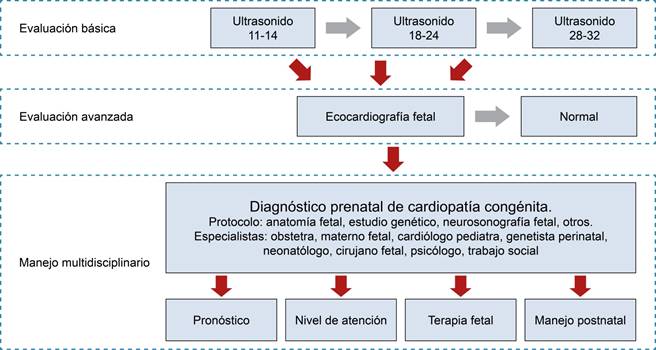

Como parte del estudio de primer trimestre, realizado habitualmente entre la semana 11 y 14 de gestación, se realiza una evaluación básica del corazón fetal. La evaluación incluye dos planos: el corte de cuatro cámaras y el corte de tres vasos y tráquea con Doppler color (Figura 1).5 Un protocolo con dichos cortes mostró una detección de 37 y 57% de defectos cardiacos mayores.6 En esta edad gestacional también se realiza la evaluación de marcadores ecográficos indirectos de cardiopatía (translucencia nucal aumentada, ducto venoso con onda A reversa, y válvula tricúspide con insuficiencia severa).5

Figura 1: Evaluación básica del corazón fetal en el primer trimestre con Doppler color: A) corte de cuatro cámaras; B) corte de tres vasos y tráquea.